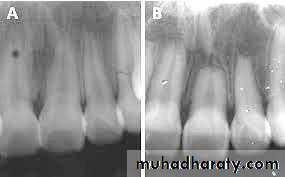

Periapical granuloma

Periapical granuloma is one of the most common sequelae of pulpitis. It is usually described as a mass ofchronically inflamed granulation tissue found at the apex of nonvital tooth.

Etiology

Periapical granuloma is a cell mediated response to pulpal bacterial products. Bacterial and toxins cause mild irritation of periapical tissues. This leads to cellular proliferation and thus granuloma formation.Clinical Features

• Most of the cases are asymptomatic but sometimes pain and sensitivity is seen when acute exacerbation occurs• Tooth is not sensitive to percussion

• No mobility

• Soft tissue overlying the area may/may not be tender

• No response to thermal or electric pulp test

• Mostly, lesions are discovered on routine radiographic examination.

Radiographic Features

• Mostly discovered on routine radiographic examination• The earliest change in the periodontal ligament is found to be thickening of ligament at the root apex

• Lesion may be well circumscribed or poorly defined

• Size may vary from small lesion to large radiolucency exceeding more than 2 cm in diameter.

• Some amount of root resorption has been reported.